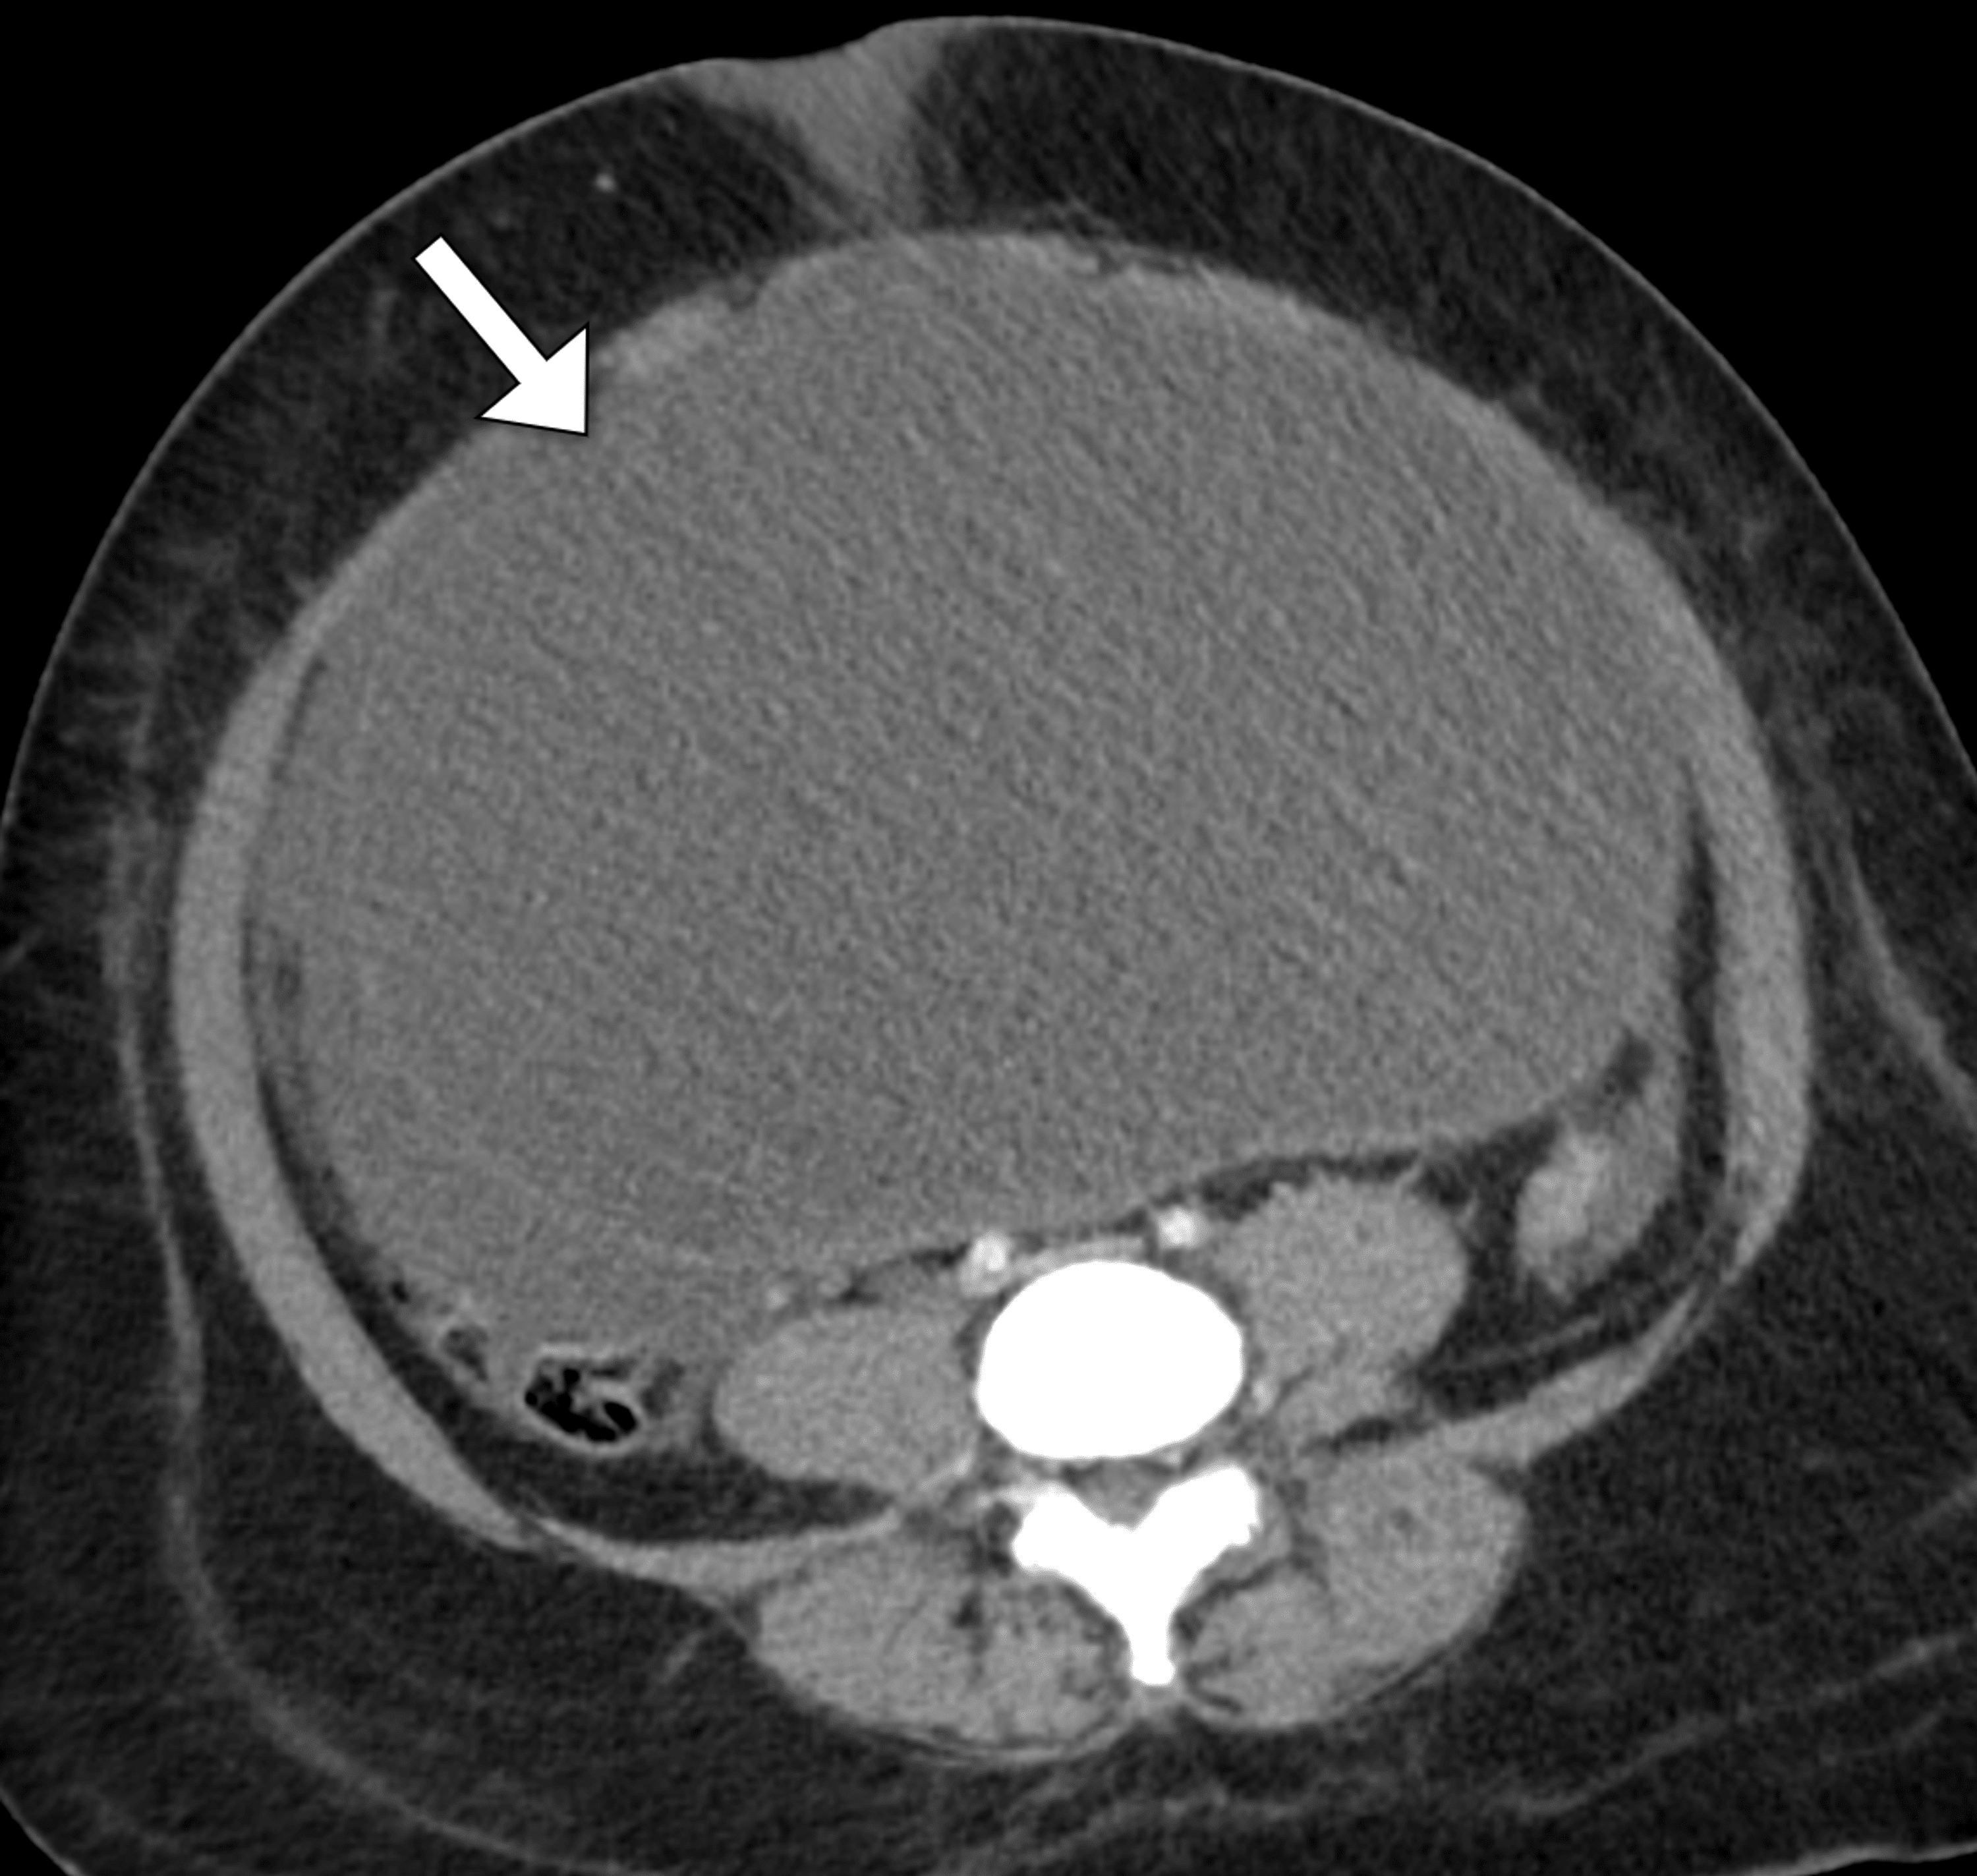

Diagnostics Free FullText Abdominal Compartment Syndrome in Acute Compartment Syndrome Shock Compartment syndrome happens when there’s too much pressure around your muscles. Acute compartment syndrome (acs) is caused by tissue ischemia due to increased pressure within a fascial compartment. Acute compartment syndrome, or acs, is a condition that happens when pressure builds up in a group of muscles. Compartment syndrome occurs when increased pressure within a compartment compromises the circulation and. Compartment Syndrome Shock.